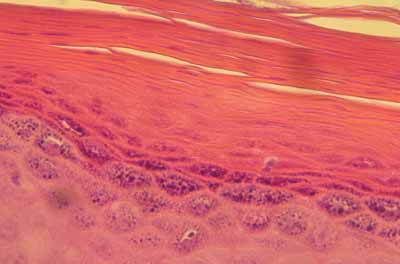

Il montre une hypergranulose diffuse et une hyperkératose parakératosique diffuse, se traduisant par la formation d’une couche cornée parakératosique, diffuse très compacte, devenant superficiellement, sur certaines biopsies, pustuleuse, avec très en surface de cette couche cornée, possibilité d’accumulation d’un feutrage bactérien abondant.

cas-de-parakeratose-granulaire9Photo 9 : Hypergranulose et parakératose

cas-de-parakeratose-granulaire10Photo 10 : Vue rapprochée de l’hypergranulose

de la couche granuleuse